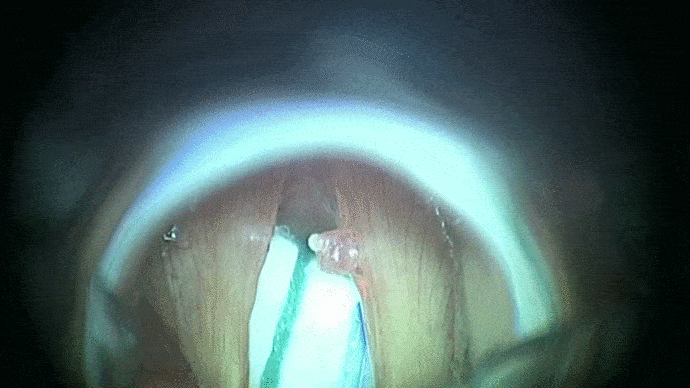

La phono-chirurgie et la micro-chirurgie laryngée est une intervention sous anesthésie générale réalisée en laryngoscopie directe en suspension et permet :

- de préciser l’extension d’une lésion laryngée

- de réaliser un prélèvement ou biopsie

- d’effectuer un geste thérapeutique laryngé pour une petite tumeur ou un polype par exemple.

L’instrumentation comporte une suspension qui libère les mains de l’opérateur. Le laryngoscope est introduit par la bouche et s’appuie sur les dents par l’intermédiaire d’une protection dentaire. Les instruments sont utilisés sous contrôle du microscope opératoire ou des optiques. Un repos vocal post opératoire vous sera dans certains cas préconisé.